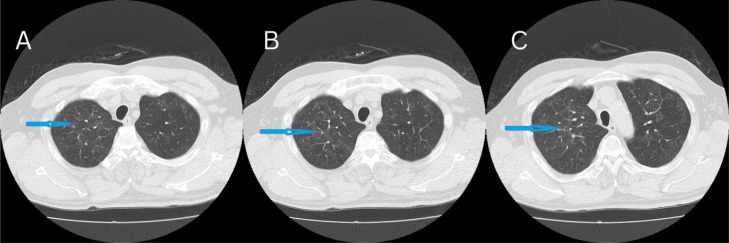

Hypersensitivity Pneumonitis (HP) is an allergic interstitial lung disease that arises from type III and IV allergic reactions. During the COVID-19 outbreak, HP was established as having similar manifestations to COVID-19. In remote rural regions of Japan, where respiratory specialists are not readily accessible, HP is not always easy to differentiate, and establishing a definitive diagnosis can be challenging due to insufficient laboratory examinations. Herein, we present a case of a moderately definite diagnosis of acute non-fibrosing HP. The foundation of treatment included antigen avoidance, which necessitates a comprehensive analysis of the patient's medical history. In instances where anomalous chest imaging outcomes are observed, it is imperative to conduct a comprehensive review of the patient's medical history, and to consider the possibility of HP.